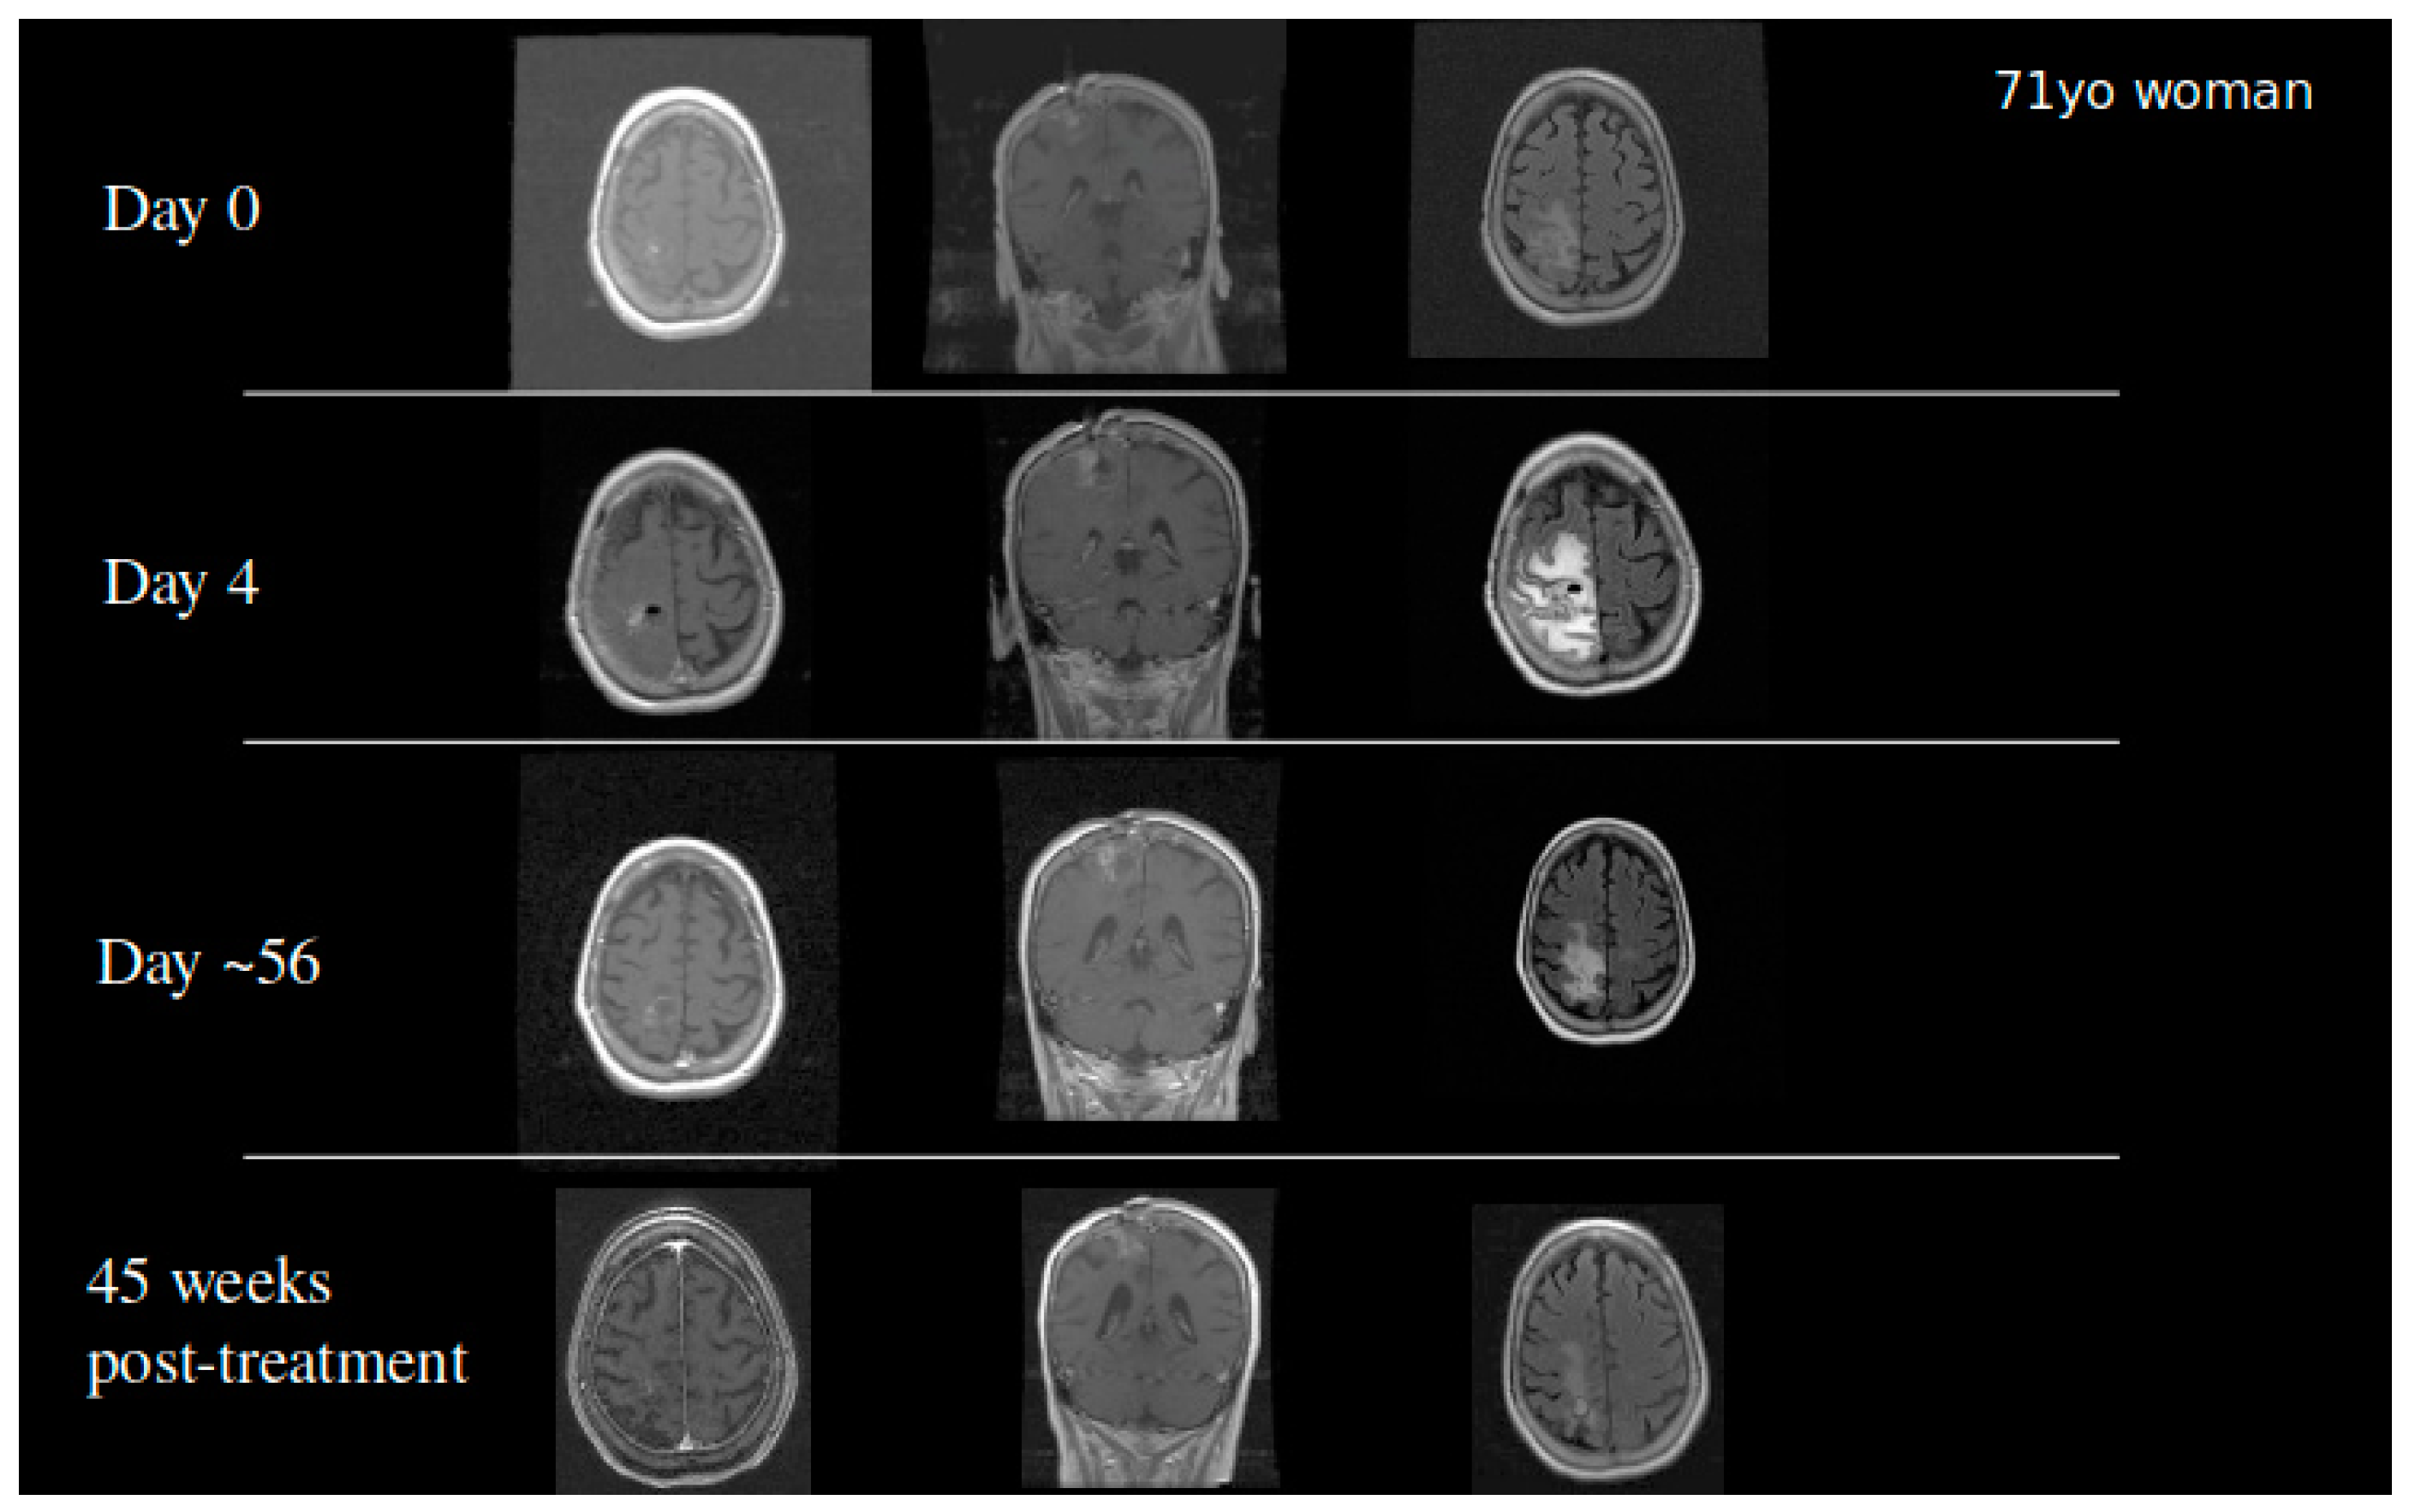

Based on the success of TPT by CED in our animal models, we received FDA approval to conduct a clinical trial in patients with recurrent malignant gliomas. Our initial Phase IB clinical trial studied 10 glioblastoma and six anaplastic astrocytoma patients in a dose escalation study to determine the maximum tolerated dose. Infusions of topotecan continued for 100 h with a flow rate of 200 µL/h. Four dose levels were studied: 0.04, 0.0667, 0.1, and 0.133 mg/mL. We did observe two events of dose limiting toxicity that established the maximum tolerated dose. Eleven out of 16 patients demonstrated either early response or pseudoprogression showing that the infusion of topotecan could lead to tumor specific cell death with minimal adverse events [42]. Patients who had an early response or pseudoprogression on MRI had a significantly improved overall survival. GBM patients in this cohort had a 20%, 2-year survival following the treatment. Two patients became long-term survivors with a survival from treatment of over 10 years [42]. To date, one patient from the cohort remains alive (Figure 4). This finding coupled with the high percentage of patients with tumor response demonstrated that further optimization of treatment regimens may require chronic dosing of therapies through the CED catheter.

Figure 4.

A 71-year-old woman who developed a parietal lobe syndrome on the fourth day of topotecan (TPT) by the CED treatment. Scans are shown at the time of treatment (day 0), at the time the dose limiting toxicity occurred (day 4), 8 weeks after treatment, and 45 weeks after treatment with approximately 90% return to her baseline neurological exam. She was progression free 3 years after the treatment and died just under 4 years post CED.